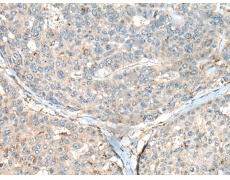

IHC positive control: |

Human gastric cancer and Human liver cancer |

IHC Recommend dilution: |

50-300 |